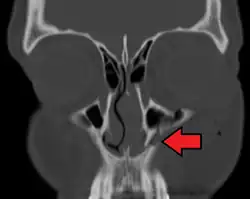

- the maxillary sinus

The maxillary sinus appears as a shallow groove on the nasal surface of the bone about the fourth month of development, but does not reach its full size until after the second dentition.

The maxillary sinus presents the appearance of a furrow on the lateral wall of the nose. In the adult the vertical diameter is the greatest, owing to the development of the alveolar process and the increase in size of the sinus.